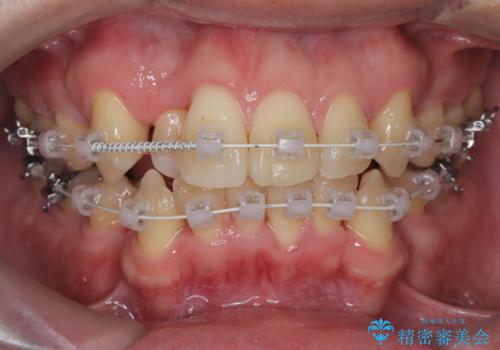

- ワイヤー(審美装置)

- 2年2ヶ月

- 10-30回